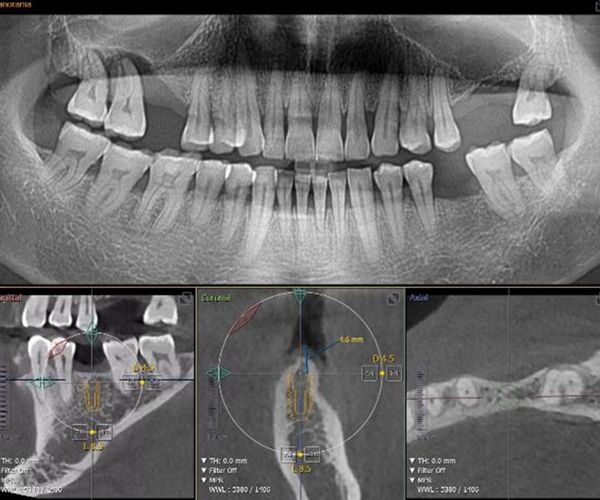

3차원 컴퓨터 모의 시술 후 절개없는 빠른 식립

3D 수술 가이드를 통한

오차 없는 초정밀 수술

네비게이션 디지털 임플란트

3D CBCT와 최신 디지털 스캐너를 이용해 채득한 구강 데이터를 기반으로 3D 모의수술 후 맞춤 제작된 수술 가이드를 사용해 미리 계획된 위치에 오차 없는 정확한 식립이 가능하기 때문에 고난이도 임플란트 케이스도 적용 가능하며, 최소침습으로 수술 시간이 짧고 체력적으로 부담이 적습니다.

3D CT&스캐너 디지털 정밀 진단

• 일반 임플란트 치아 상태 및 신경의 위치를 2D(평면)으로만 확인이 가능해 정확한 진단이 어려울 수 있음

• 3D CT를 통한 컴퓨터 분석 현재 턱 뼈와 잇몸의 상태를 3차원 입체 영상으로 확인이 가능해 정밀 진단에 따른 오차 없는 수술이 가능